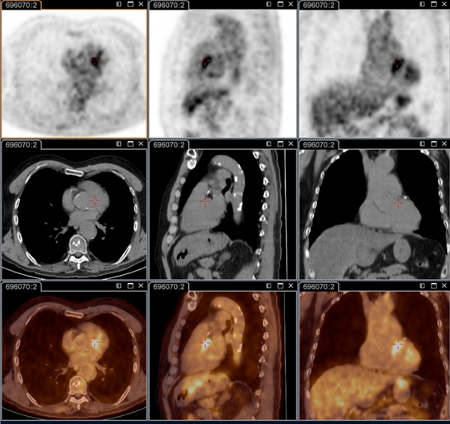

tomografia por emissão de pósitrons (PET)/tomografia computadorizada (TC) com 18-fluordesoxiglucose (FDG)

Exame

Essencial para identificar infecções focalizadas persistentes.[80]

É capaz de decifrar endocardite, infecção vascular, linfadenite e infecção osteoarticular; essas doenças não podem ser identificadas sem essa técnica.

Agora faz parte do check-up anatômico padrão em pacientes com sintomas persistentes e/ou sorologia elevada persistente e/ou reação em cadeia da polimerase positiva no sangue/soro, ou qualquer amostra com quadro clínico não consistente com infecção primária.[3]

É especificamente recomendada em pacientes: com febre Q aguda com IgG de fase 1 ≥1:800 persistente e/ou sinal de evolução desfavorável; com febre Q aguda e história de enxerto vascular ou aneurisma vascular; ou com sorologia inexplicada (IgG na fase 1 ≥1:800) ou suspeita clínica de infecção persistente.

Isso também é útil para identificar infecção em pacientes com prótese vascular e/ou aneurisma, e para identificar candidatos a cirurgia de ressecção dos tecidos vasculares infectados.[Figure caption and citation for the preceding image starts]: Endocardite por febre Q diagnosticada na PET: PET/TC com 18-fluordesoxiglucose. Neste paciente assintomático com história de valva cardíaca e sorologia elevada, a PET permitiu diagnosticar endocardite aórtica na valva nativa com aneurismas micóticos da aorta torácica e lombarInstitut Hospitalo-Universitaire Méditerranée Infection (obtido consentimento do paciente) [Citation ends].

[Figure caption and citation for the preceding image starts]: Aneurisma micótico na aorta torácica da febre Q diagnosticado na PET: PET/TC com 18-fluordesoxiglucose. Neste paciente assintomático com história de valva cardíaca e sorologia elevada, a PET permitiu diagnosticar endocardite aórtica na valva nativa com aneurismas micóticos da aorta torácica e lombarInstitut Hospitalo-Universitaire Méditerranée Infection (obtido consentimento do paciente) [Citation ends].

[Figure caption and citation for the preceding image starts]: Aneurisma micótico na aorta lombar da febre Q diagnosticado na PET: PET/TC com 18-fluordesoxiglucose. Neste paciente assintomático com história de valva cardíaca e sorologia elevada, a PET permitiu diagnosticar endocardite aórtica na valva nativa com aneurismas micóticos da aorta torácica e lombarInstitut Hospitalo-Universitaire Méditerranée Infection (obtido consentimento do paciente) [Citation ends].

Resultado

positivo na infecção focalizada persistente (por exemplo, valva cardíaca, foco vascular da linfadenite, linfonodos, foco osteoarticular)